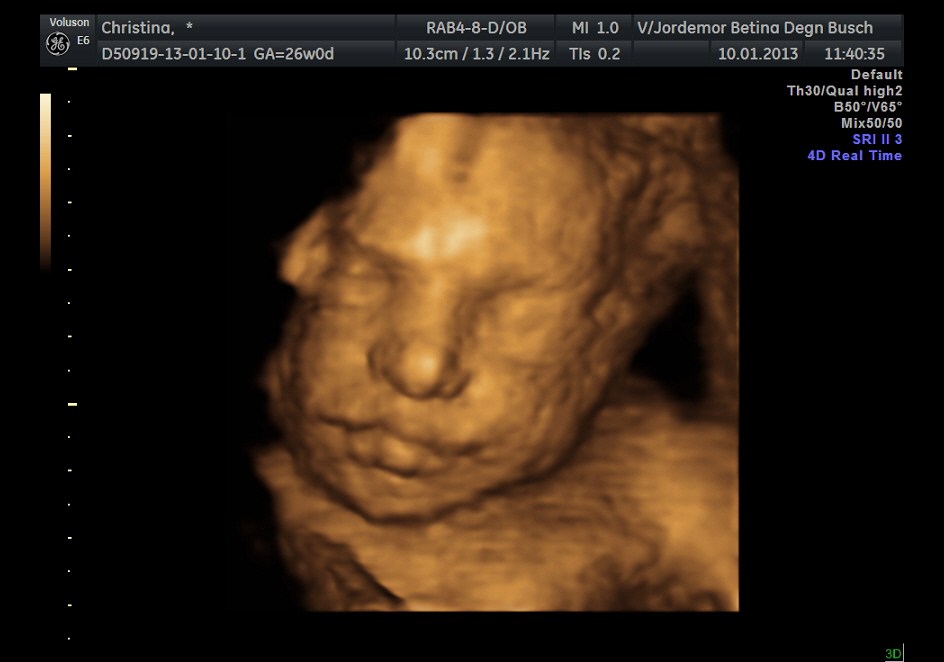

er i dag 26+0 og baby er helt normal. og selvfølgelig slår hjertet, men det vidste jeg nu godt for mærker hele mange mange gange om dagen

hun vejer 819 gram..

hun gav en lille smags prøve på 3d billeder da jeg nævnte at vi vil komme ind til hende når vi ramte uge 28+..